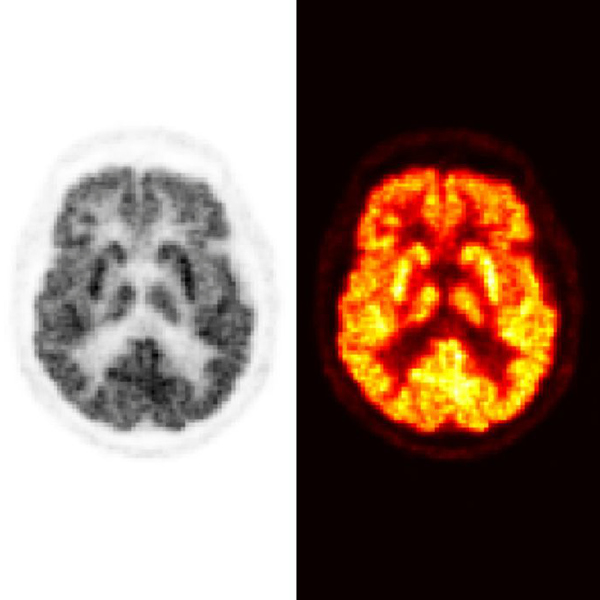

On Thursday, 29 February, Klara Leffler, Department of Mathematics and Mathematical Statistics, will defend her thesis entitled The PET Sampling Puzzle: Intelligent data sampling methods for positron emission tomography. The defence takes place at 9:00 a.m. in room BIO.E.203 – Aula Biologica, Umeå University.